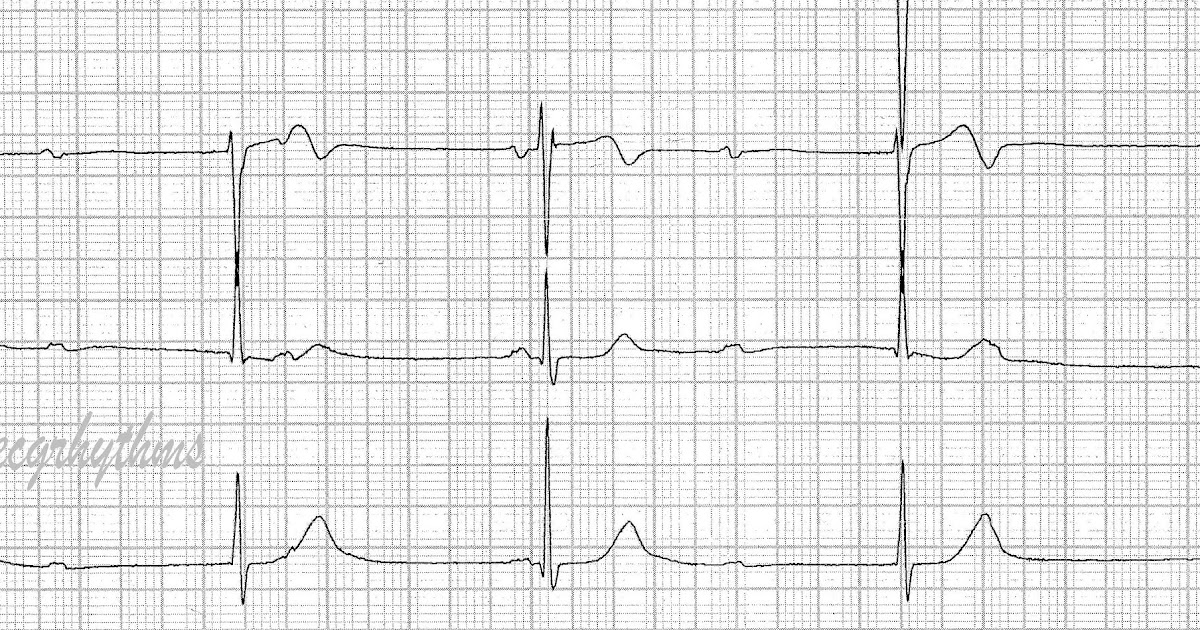

Heart Block Ecg Practice . Web this ekg practice test is designed to help you learn to recoginze all of the ekg rhythms that you will encounter. Web ecg features of complete heart block. Web with our ekg strip practice drills, it is easy to engage in fast, interactive learning. Pr interval > 200ms (five small squares) there is delay, without interruption, in conduction from atria to ventricles. Severe bradycardia due to absence of av conduction. Web this ekg rhythm practice quiz will test your knowledge on the different types. Web ekg practice learn with flashcards, games, and more — for free. This interruption of impulse transmission results in characteristic ecg The ecg demonstrates complete av dissociation,. Web atrioventricular (av) block (often referred to as “heart block”) involves the partial or complete interruption of impulse transmission from the atria to the ventricles. This page provides an introduction to heart block rhythms with links to our lessons and drills.

The ecg demonstrates complete av dissociation,. Web ecg features of complete heart block. This interruption of impulse transmission results in characteristic ecg This page provides an introduction to heart block rhythms with links to our lessons and drills. Web with our ekg strip practice drills, it is easy to engage in fast, interactive learning. Web atrioventricular (av) block (often referred to as “heart block”) involves the partial or complete interruption of impulse transmission from the atria to the ventricles. Pr interval > 200ms (five small squares) there is delay, without interruption, in conduction from atria to ventricles. Web this ekg practice test is designed to help you learn to recoginze all of the ekg rhythms that you will encounter. Web this ekg rhythm practice quiz will test your knowledge on the different types. Severe bradycardia due to absence of av conduction.

ECG Rhythms Advanced Heart Block Heart Block Ecg Practice The ecg demonstrates complete av dissociation,. Pr interval > 200ms (five small squares) there is delay, without interruption, in conduction from atria to ventricles. Web atrioventricular (av) block (often referred to as “heart block”) involves the partial or complete interruption of impulse transmission from the atria to the ventricles. Severe bradycardia due to absence of av conduction. Web this ekg. Heart Block Ecg Practice.

ECG Rhythms Complete Heart Block or Not? Heart Block Ecg Practice Web ekg practice learn with flashcards, games, and more — for free. The ecg demonstrates complete av dissociation,. Web ecg features of complete heart block. Web this ekg rhythm practice quiz will test your knowledge on the different types. Severe bradycardia due to absence of av conduction. Web atrioventricular (av) block (often referred to as “heart block”) involves the partial. Heart Block Ecg Practice.

ECG Rhythms Is this Complete Heart Block? Heart Block Ecg Practice This page provides an introduction to heart block rhythms with links to our lessons and drills. Web with our ekg strip practice drills, it is easy to engage in fast, interactive learning. Web atrioventricular (av) block (often referred to as “heart block”) involves the partial or complete interruption of impulse transmission from the atria to the ventricles. Web ecg features. Heart Block Ecg Practice.

Complete (3°) Heart Block EKG RK.MD Heart Block Ecg Practice Web this ekg rhythm practice quiz will test your knowledge on the different types. This interruption of impulse transmission results in characteristic ecg Web with our ekg strip practice drills, it is easy to engage in fast, interactive learning. Web ecg features of complete heart block. Pr interval > 200ms (five small squares) there is delay, without interruption, in conduction. Heart Block Ecg Practice.